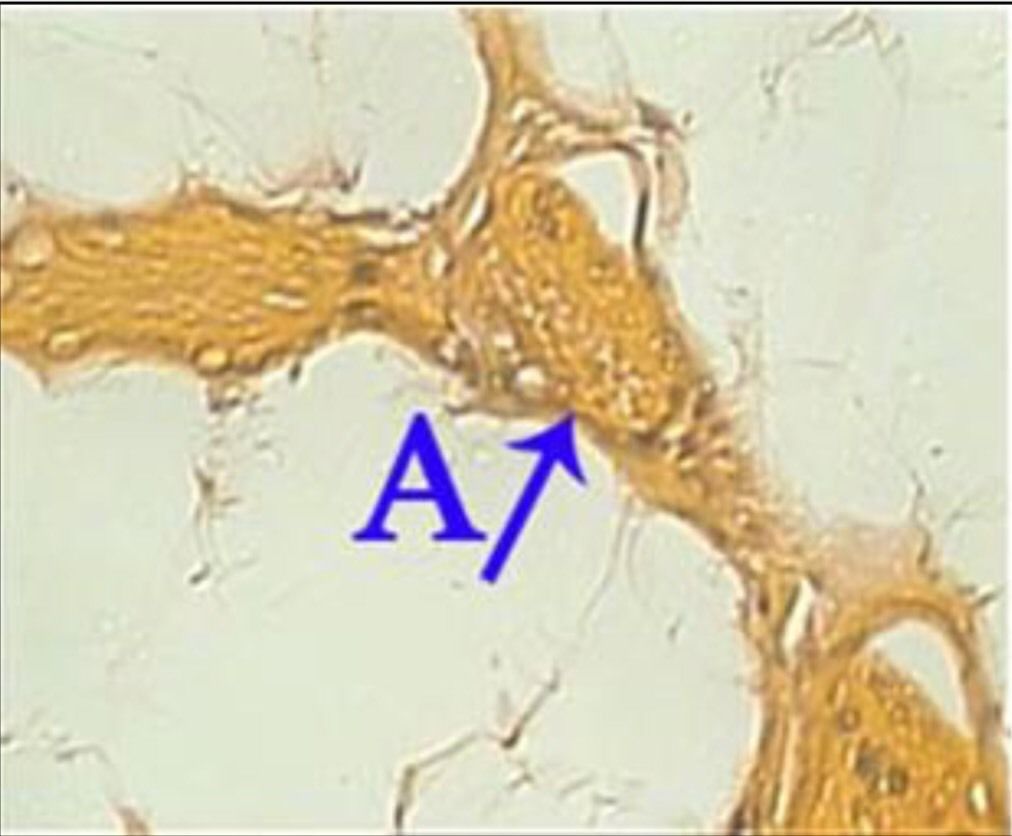

Question 16

Question

What is the correct answer at point A?

Answer

• - veine Centro lobulaire

• - travée hépatocytaire

• - dépôt amyloïde péricentrolobulaire

• - substance amyloïde intercellulaire

• - dépôt amyloïde dans l’espace porte

Question 17

What is the correct answer at point B?

Question 18

What is the correct answer at point C?

Question 19

What is the correct answer at point D?

Question 20

What is the correct answer at point E?